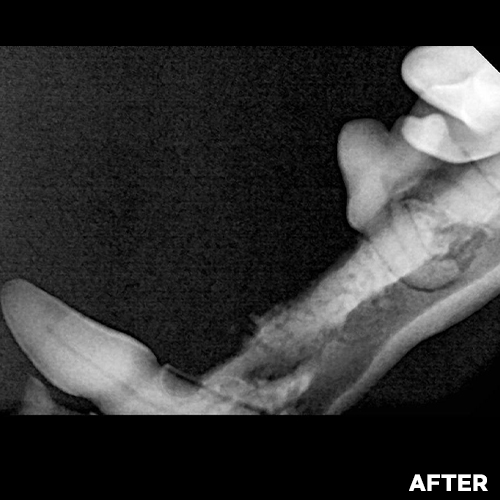

[심장병 강아지 골절뼈, 치아 제거 후 뼈이식]

샘플